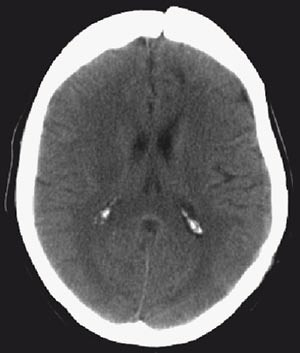

I løpet av første døgn i sykehus utviklet pasienten afasi og økende parese i høyre sides ekstremiteter. Natt til femte døgn i sykehus tilkom redusert bevissthet, og i løpet av noen få timer ble hun komatøs med blodtrykksstigning til 230/130 mm Hg og bradykardi (40 slag per minutt). Hun utviklet venstre oculomotoriusparese som tegn på truende herniering. Cerebral CT viste betydelig ødemutvikling med utslettede sulci over konveksiteten, midtlinjeoverskytning mot høyre og nesten global okklusjon av de basale cisterner (fig 2).